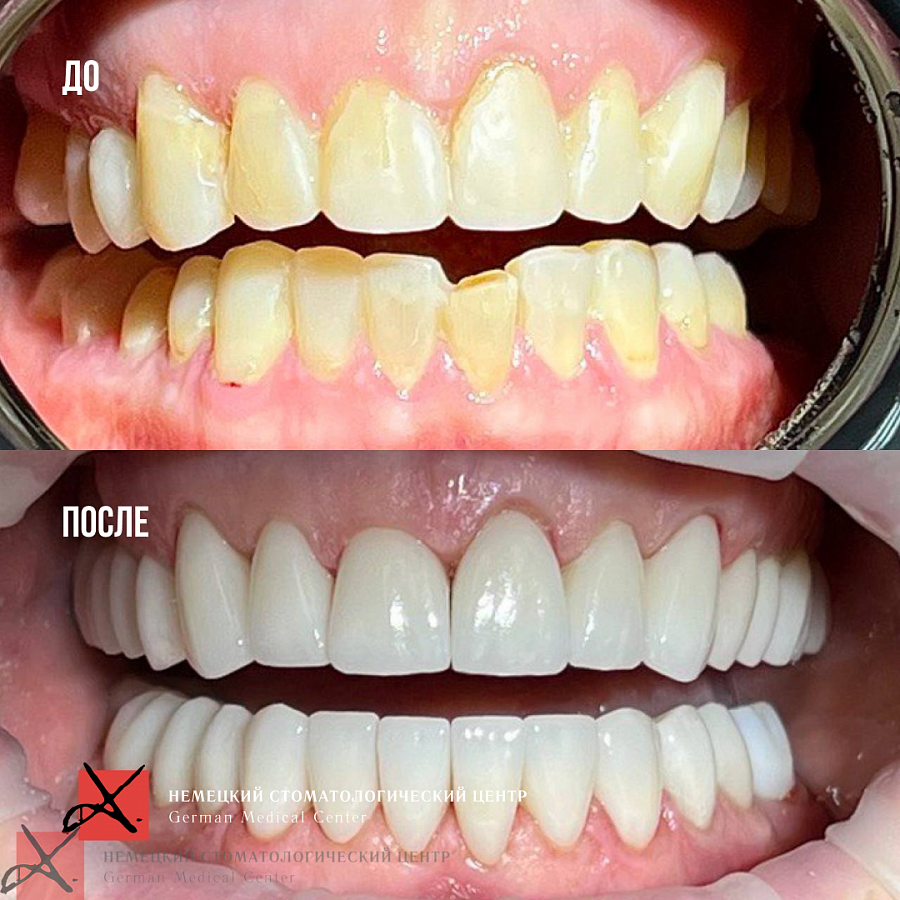

Пациентка обратилась с жалобами на неудобство и дискомфорт в области суставов. Диагностика выявила, что проблема связана с некачественным лечением и протезированием, которое вызвало снижение сустава нижней трети лица и изменение позиции других элементов ВНЧС.

1. Изготовили 3D-модели в новой терапевтической высоте.

2. Провели санацию зубов.

3. Далее сделали примерку будущих конструкций и на основании прототипа выполнили тотальное протезирование в новой терапевтической высоте в центральном соотношении челюстей.

После чего суставы встали в правильное положение, ушел дискомфорт при жевании, а лицо стало более подтянутым (антиэйдж стоматология в действии!)

Пациентка выбрала цвет зубов, который значительно светлее её естественного цвета. Но в результате всё смотрится очень натурально.

Пациентка очень довольна результатом!

Результат лечения